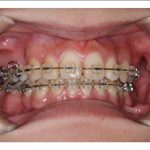

2) 矯正中の状態

叢生(そうせい…歯がデコボコしたり、重なりあって生えていたりする状態)

開咬(かいこう…奥歯はしっかり噛んでいるが、上下の前歯が噛まずに隙間がある状態)